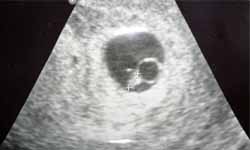

лодный мешок узи

Плодный мешок узи 87 фото